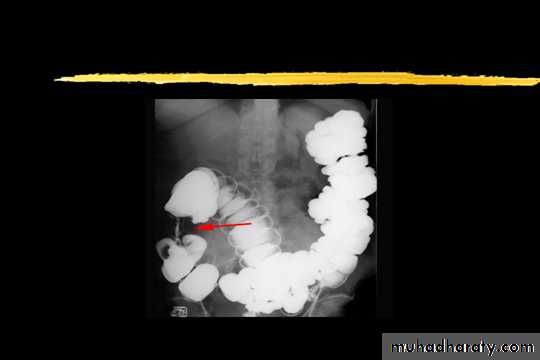

congenital megacolon (Hirschprung disease )

• There is one or more segment of colon devoided from innervation resulting in constriction with proximal dilatation of rest of colon due to weak innervation .• The agangloinic segment usually short , at or near the recto- sigmoid junction .

congenital mega colon

• Rarely the whole colon can be affected result in micro-colon .• 5. Clinically the patient suffering from constipation and abdominal distention since birth .

• 6. The value of Ba Enema is to spot the narrow segment especially prior to surgery .

• 7. Instant Ba Enema is usually done and the Barium used is usually hypertonic .

• Views of particular importance include:

• early filling views that include rectum and sigmoid colon allowing for rectosigmoid ratio to be determined.

• transition zone